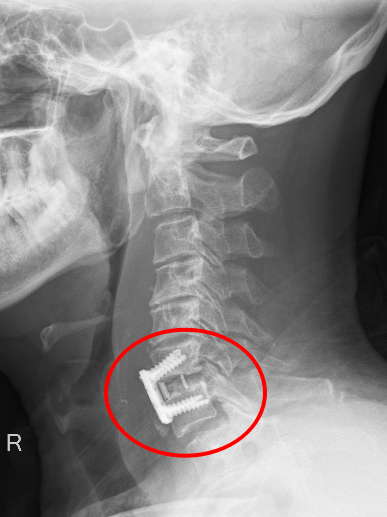

患者朱先生因意外從高處墜落,頸部劇痛、四肢麻木無力,急診入院后經CT及MRI檢查確診為第6頸椎骨折脫位伴脊髓損,隨時可能引發呼吸衰竭或永久性癱瘓。傳統保守治療風險極高,骨科主任彭李華主任醫師及脊柱專業組長張利強,迅速組織多學科會診,結合國際最新指南與患者個體情況,果斷制定“前路頸椎間盤切除+植骨融合內固定術”方案,以微創技術最大限度減少神經損傷,脊髓受壓明顯減輕,重建頸椎穩定性。

術后影像顯示,頸椎序列完美復位,內固定位置精準,患者次日即感雙上肢麻木緩解,肌力較術前明顯改善,術后第二天,患者頸部及雙上肢疼痛癥狀消失,在頸托保護能自主下床行走,術后一周痊愈出院。